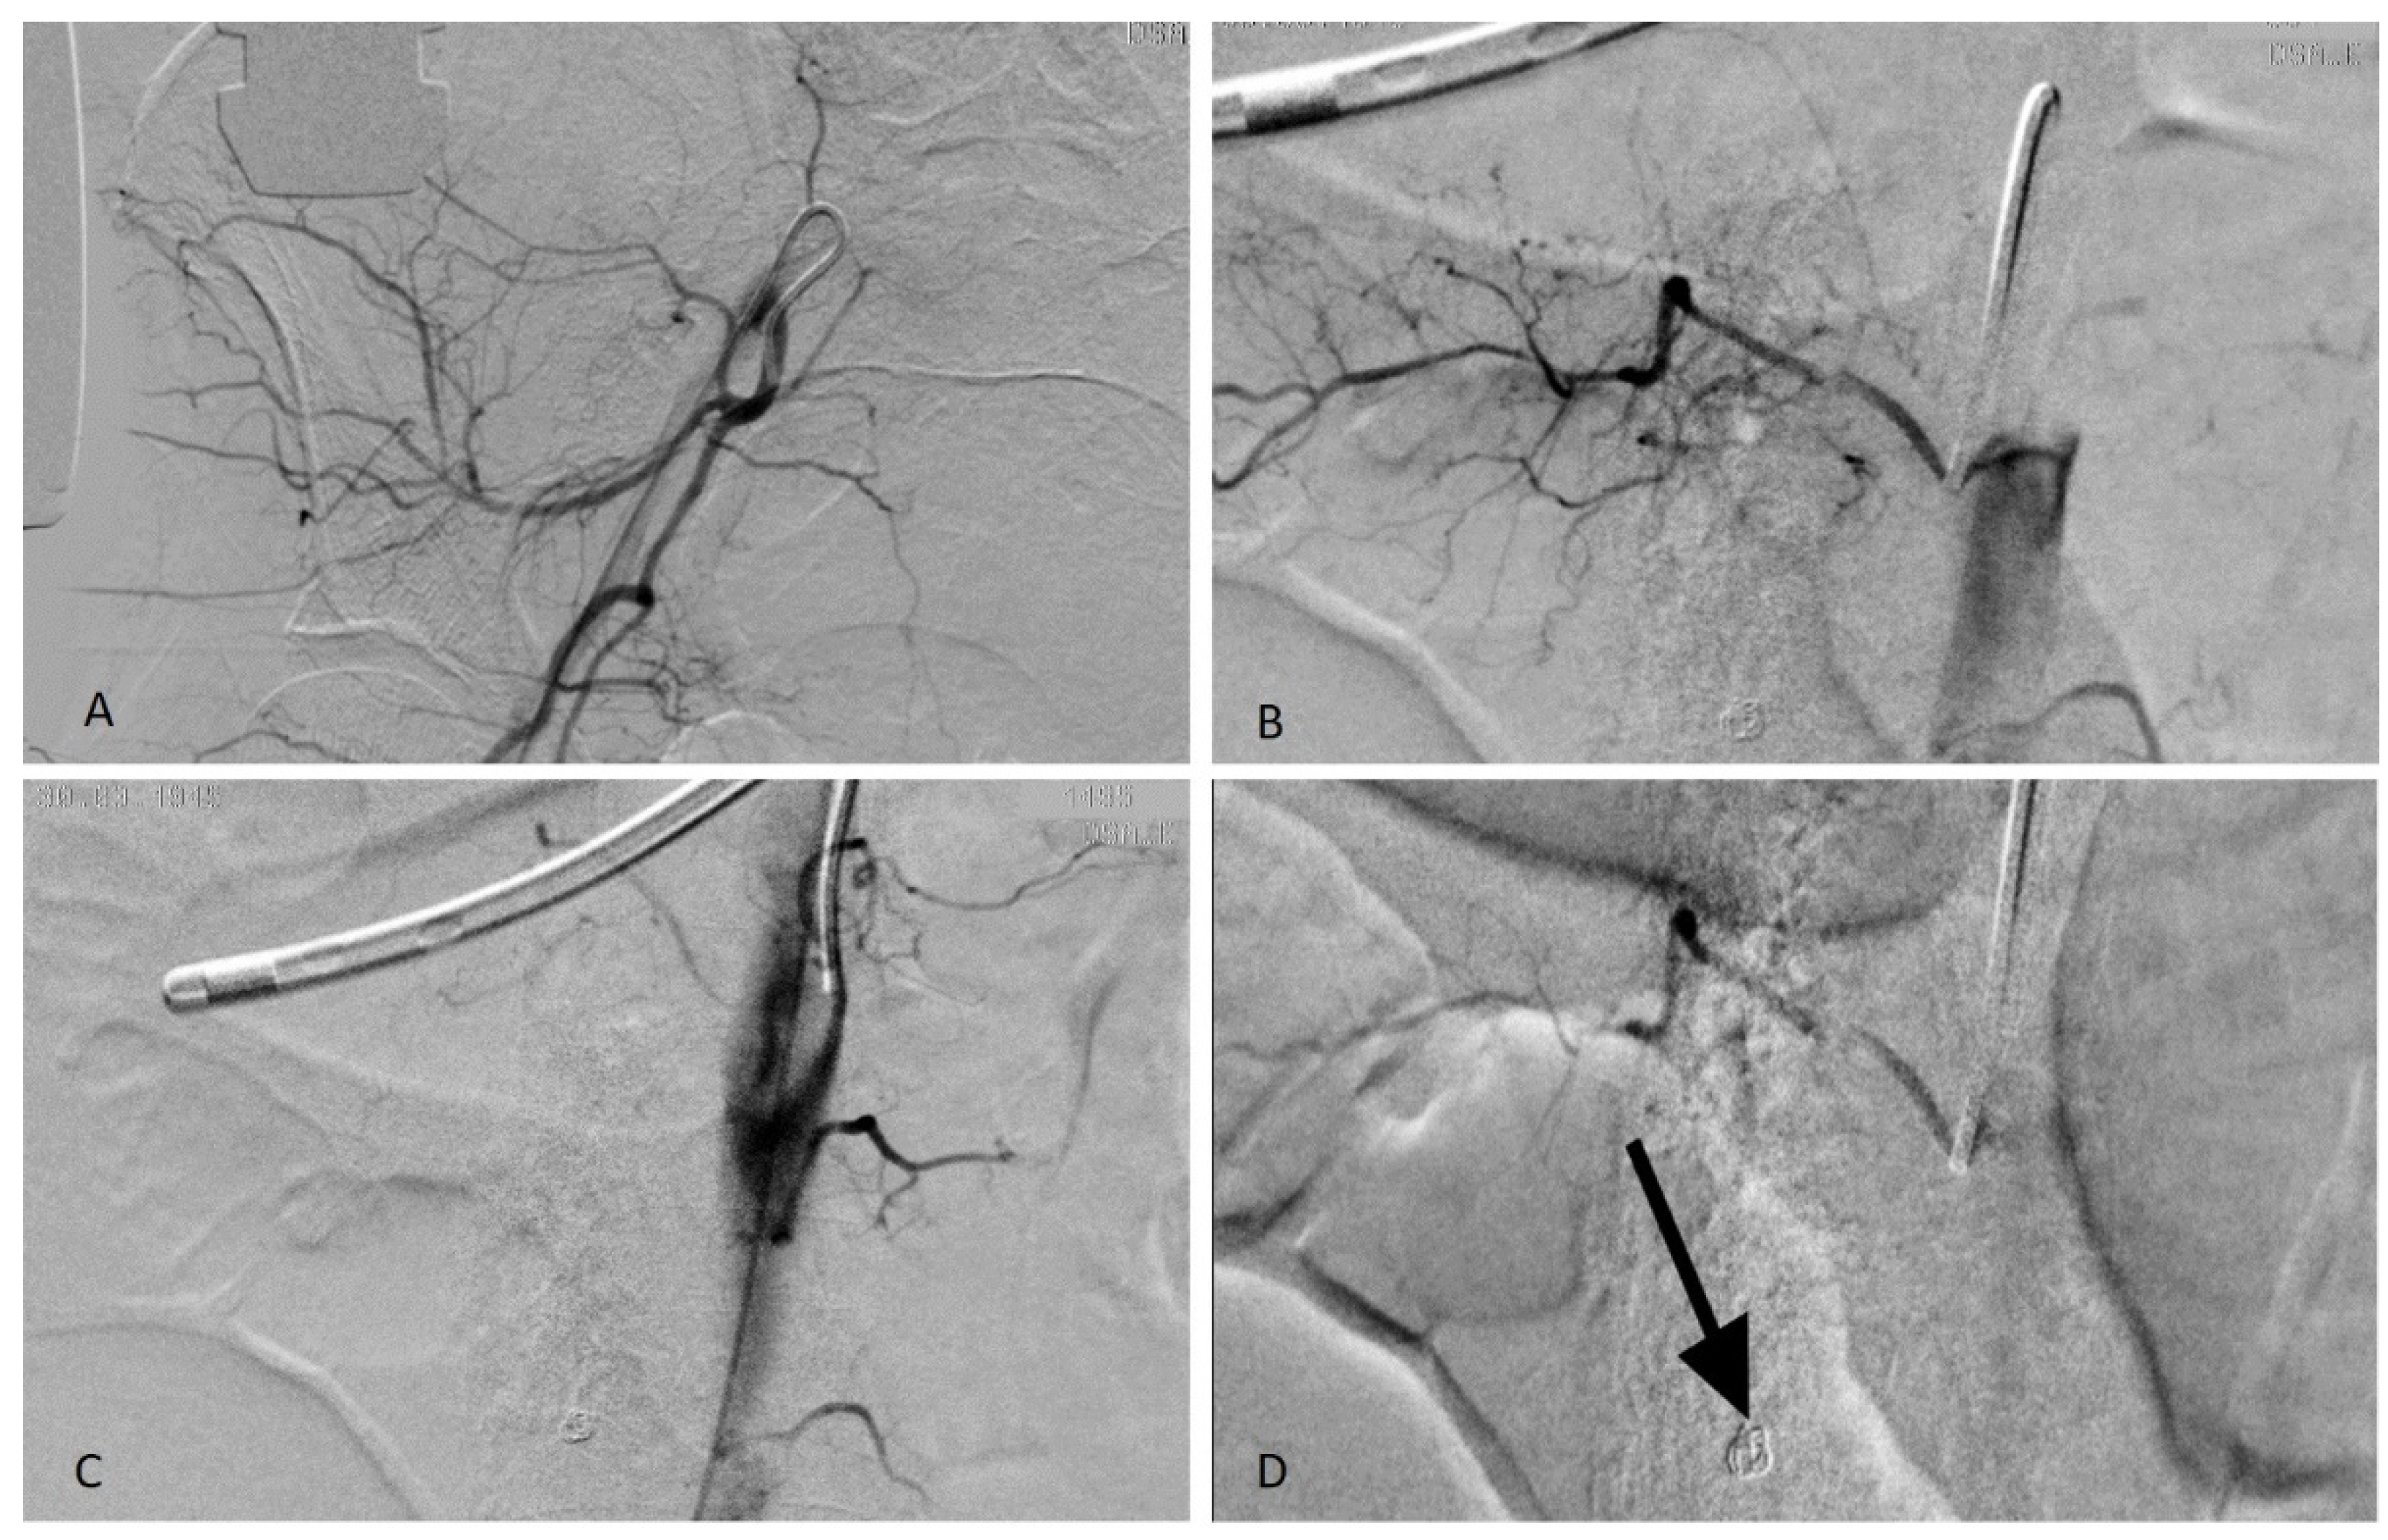

Figure 4.

(A) Catheterism of the right hypogastric artery to reach the right ileo-lumbar artery (anastomotic territory); (B) Lumbar artery catheterization showing tiny bleeding spots; (C) Post-embolization angiogram: right lumbar arteries occluded; (D) Stop flow post embolization with particles (PVA contour 350–500) in the 4th lumbar artery and coil in the 5th lumbar artery (arrow).